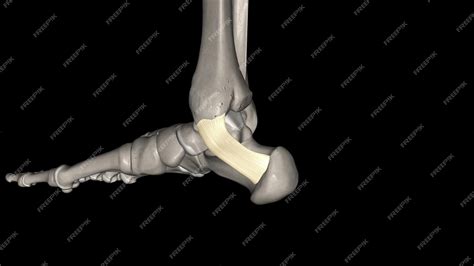

Anatomical view of the ankle and foot structure

The flexor retinaculum is a thick, fibrous band that stretches from the medial malleolus—the bony prominence on the inside of your ankle—to the medial tubercle of the calcaneus, or heel bone. Its primary purpose is to act as a ligamentous sheath, binding down the tendons of the deep muscles of the posterior compartment of the leg.